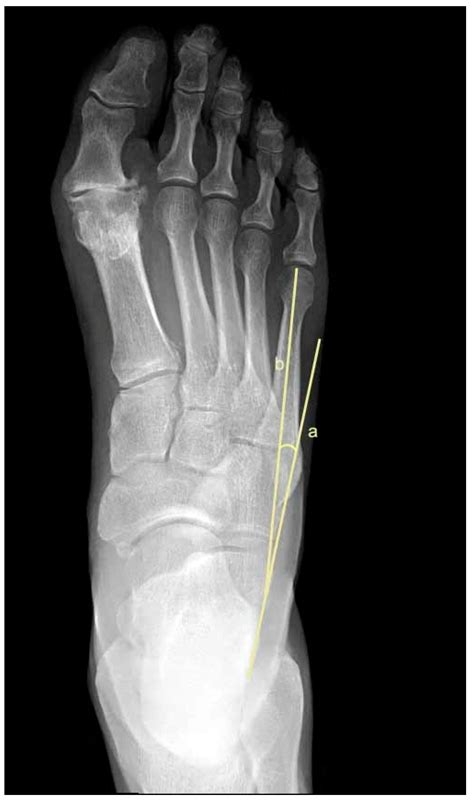

Diagnosing Metatarsus Varus Adductus

Diagnosing Metatarsus Varus Adductus typically involves a physical examination by a healthcare provider. The doctor will assess the child's gait, foot alignment, and range of motion. In some cases, imaging tests such as X-rays or MRI scans may be ordered to rule out other conditions or to assess the severity of the deformity.